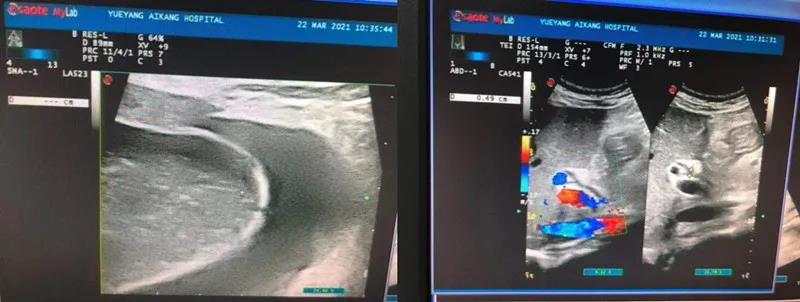

彩超檢查結(jié)果顯示:膽囊腫大、膽囊結(jié)石、急性膽囊炎

劉主任得知檢查結(jié)果后,迅速請普外科醫(yī)生會診。普外科周旭陽主任看到彩超結(jié)果單,提出需盡快手術(shù),否則隨時(shí)有穿孔的危險(xiǎn)。而劉主任則擔(dān)心手術(shù)會發(fā)生產(chǎn)褥期感染,影響產(chǎn)后恢復(fù)。然而周主任的診療方案很快消除了劉主任的擔(dān)憂,張女士被迅速轉(zhuǎn)入普外科。